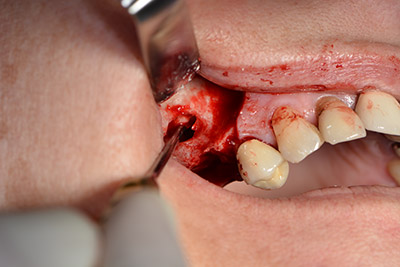

En el siguiente paso se efectúa la elevación del suelo del seno maxilar, a la vez que se coloca el implante. Para la fenestración lateral de la pared del seno maxilar Implantmed también cuenta con un ajuste predefinido en la primera posición.

La ventana se crea a una velocidad de 35.000 rpm y, a continuación, la membrana de Schneider se prepara en sentido craneal (figuras 13 a 14).